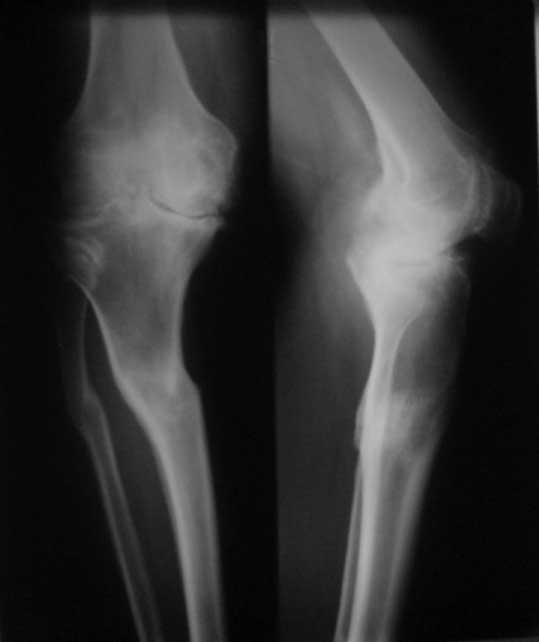

У пациента 50 лет имеется разгибательная контрактура через 8 меспосле ТКА. Уважаемые коллеги. Пациент 8 мес после операции ТКА, в анамнезе – неправильно сросшийся перелом голени, коррекция оси (снимки прилагаются. В настоящее время имеется разгибательная контрактура 10/5/0, на операционном столе было 90/0/5, на момент выписки движения 50/0/0 в надежде на дальнейшую разработку. До эндопротезирования 40/10/0. Глубокая инфекция исключена. Ротация бедренного компонента в норме (по КТ). Вопросы: насколько для такого ограничения критична некорректная установка б/б компонента (я намерял 7 град)? Причина нынешнего состояния, артрофиброз? Какие действия следует предпринять, удаление рубцов, релиз головок 4-главой мышцы? Что-либо другое, ваше мнение? С уважением, Максим Агалаков, Екатеринбург.

а вы уверены, что это артрофиброз, а не patella baja

Низковат, соласен. Соориентируетесь при операции, если ограничивает движения, перенести бугристость или Z-образная тенотомия связки надколенника, артросокпический артролиз обязательно.